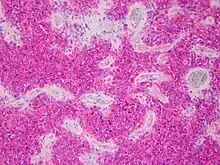

Aspect microscopique

Les sarcomes d'Ewing, et plus généralement les tumeurs neuroectodermiques primitives (PNET), montrent une prolifération d'architecture diffuse, composée de petites cellules rondes au rapport nucléocytoplasmique élevé[5].